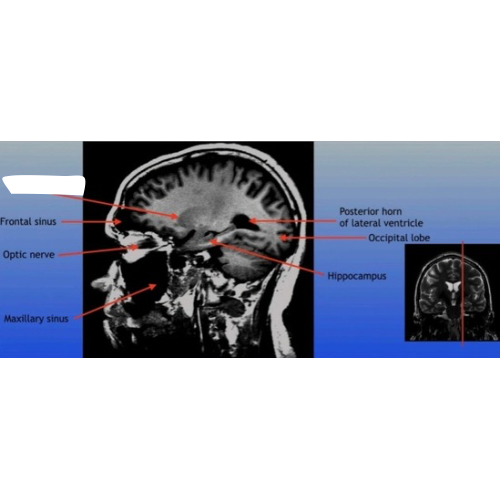

Frontal Sinus

A paired cavity located within the frontal bone, above the eyes, that plays a role in sinus drainage and resonance of the voice.

Optic Nerve

The bundle of nerve fibers that transmits visual information from the retina to the brain. It plays a crucial role in the sense of sight.

Maxillary Sinus

A paired cavity located within the maxilla, situated below the eyes, that contributes to sinus drainage and helps lighten the weight of the skull.

Posterior Horn of Lateral Ventricle

The posterior part of the lateral ventricle, involved in the production and circulation of cerebrospinal fluid within the brain.

Hippocampus

A critical region in the brain associated with memory formation and spatial navigation, located in the medial temporal lobe.